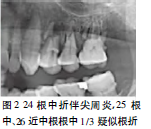

X线片示:24根中折,两断端间移位约1.5mm,根尖区可见低密度影;25根中1/3、26近中根根中1/3处疑似根折,但根尖周膜腔清晰,硬板完整,上颌牙槽骨骨小梁明显减少,密度减低(图2)。